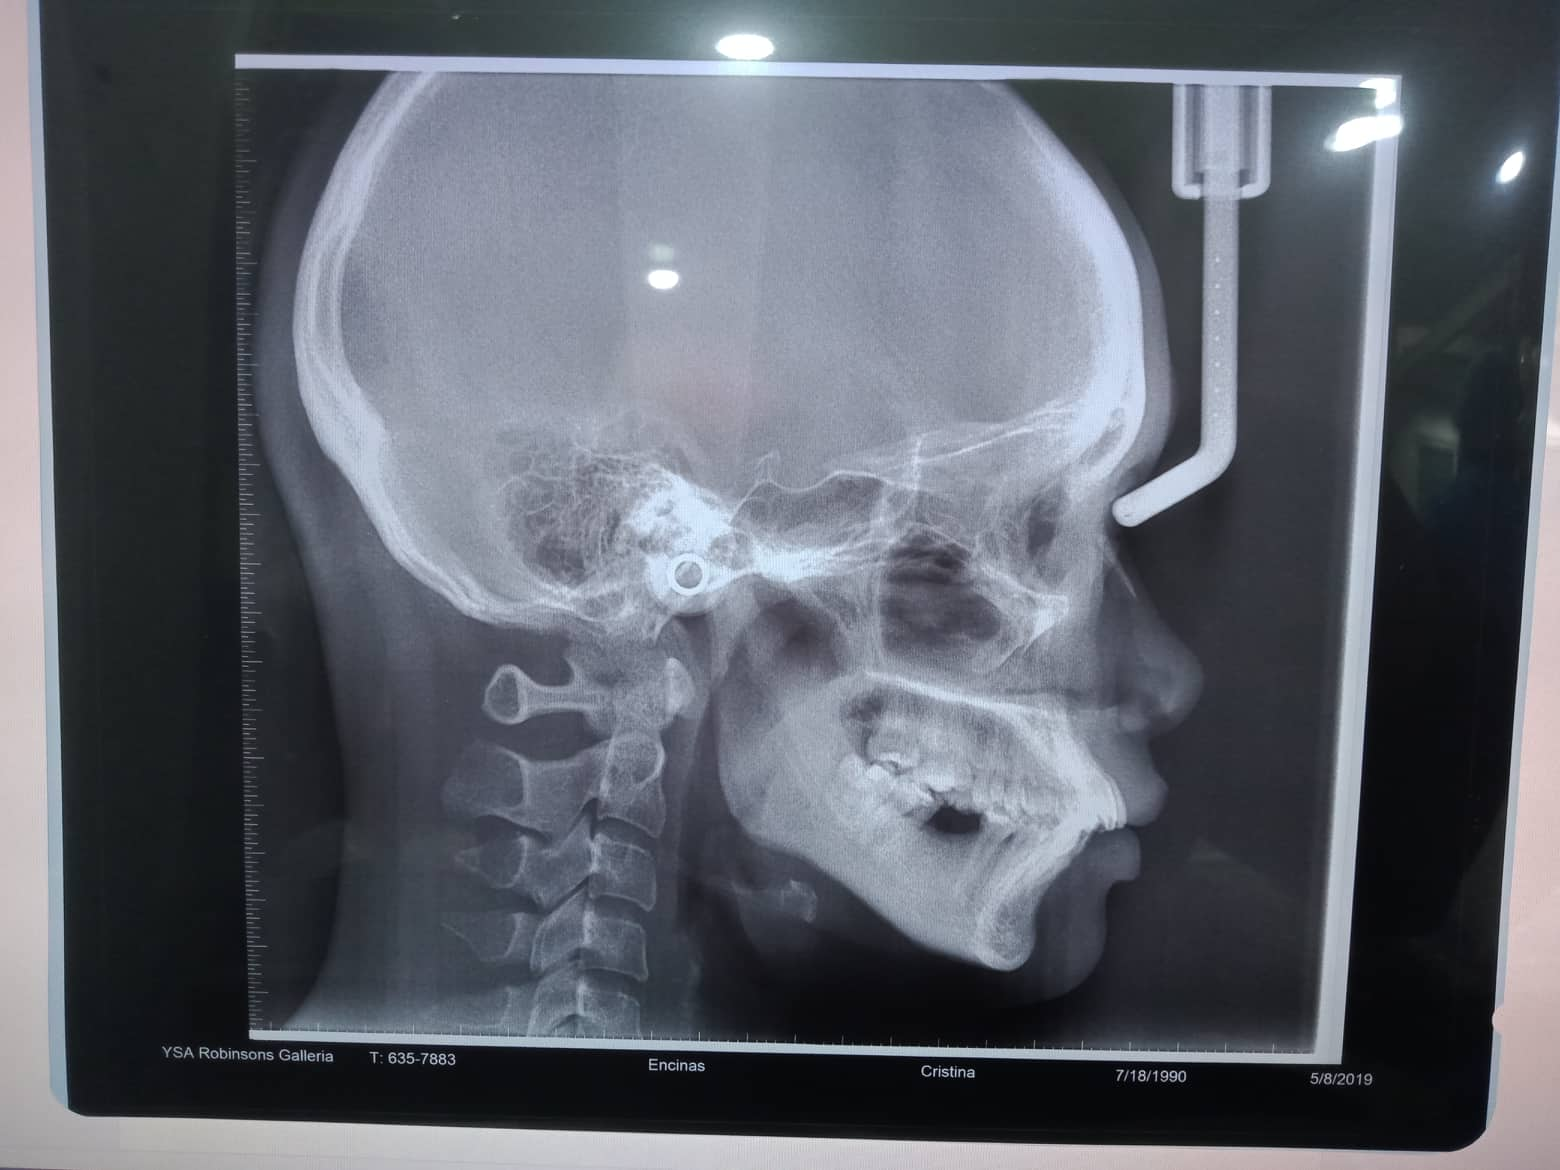

Edit Record Check our patient data records. Add patient information Patient Info Profile picture Last Name First Name Middle Name Birthdate Age Street Barangay City Country Zip Code Contact number Email Procedure 10/16/21 adj 16*22U/L extrude 44- chipmunk double elastic chain and power o upper to left 12/16/21 - chain upper/ 16*22 uL ss s-elastic 44 to 13, 45 to 14- chipmunk 1/25/22- s elastic on right q/ box elastic R Quad- fox. R quadrant n 16 niti 02/11/22- chipmunk s elastic- 13 to 44/ 14 to 45- same wire 3/18/22-chipmunk 13-44/ 14-45/ rabbit elastic box- 23-24 to 33-34/ 16x16 niti lower 05/13/22 13-14 to 43- chpmnk 16x16 ss L 6/18/22- Month Of September For Removal / same wire/ 44 extrude- chipmnk 7/29/22- U same wire placed echain; L 016x022 SS close ligation; Pt concern abt midline deviation on upper arch, told her that if she wants to address the concern, she may opt for TADS, however it is time consuming and may extend her ortho tx. 8/23/22- Same wire U, stripping on 22D and 23M, Chain U, Penguin 13-33 9/27/22 - removal of braces - upper and lower impression for retainers. File 302450901_408871331368693_864463967539202601_n.jpg File 2 302318849_520060069884290_5536848649181119832_n.jpg File 3 302487020_441958927896332_8414292300474769290_n.jpg File 4 304829205_492469312712272_6122418120013648735_n.jpg File 5 File 6 File 7 File 8 File 9 File 10 File 11 File 12 File 13 File 14 File 15 File 16 File 17 File 18 File 19 File 20 Retain Record Retain Record Yes No Save Your Changes